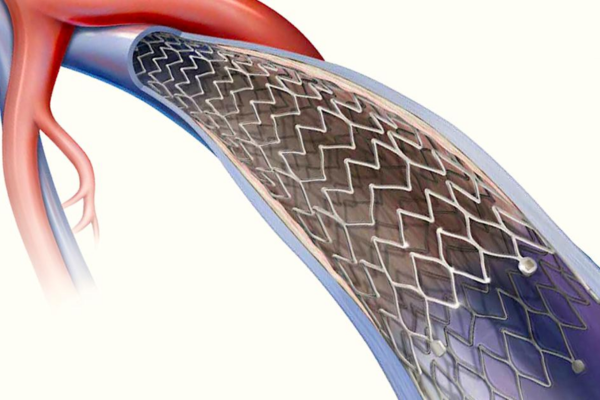

Severe or chronic pancreatitis can weaken nearby blood vessels, forming pseudoaneurysms that may rupture suddenly and cause massive internal bleeding.

Embolisation seals the weakened vessel safely, prevents rupture, controls bleeding effectively, and avoids major surgery while protecting surrounding organs.

Budd-Chiari syndrome occurs when hepatic veins or the inferior vena cava are blocked, leading to liver swelling, pain, and fluid accumulation.

Stenting restores venous outflow from the liver, relieves symptoms, improves liver function, and prevents progressive liver failure.